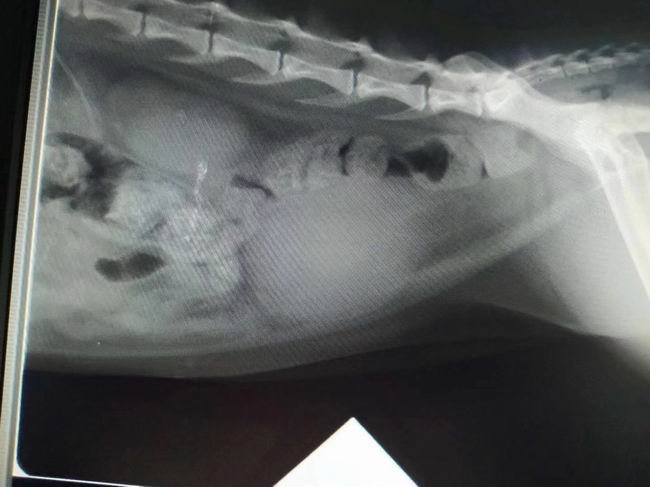

本月又一急診尿閉病例恢復(fù)/出院穩(wěn)定:黑子,母喵,尿閉,經(jīng)住院治療,體征已穩(wěn)定,主人帶回護(hù)理。